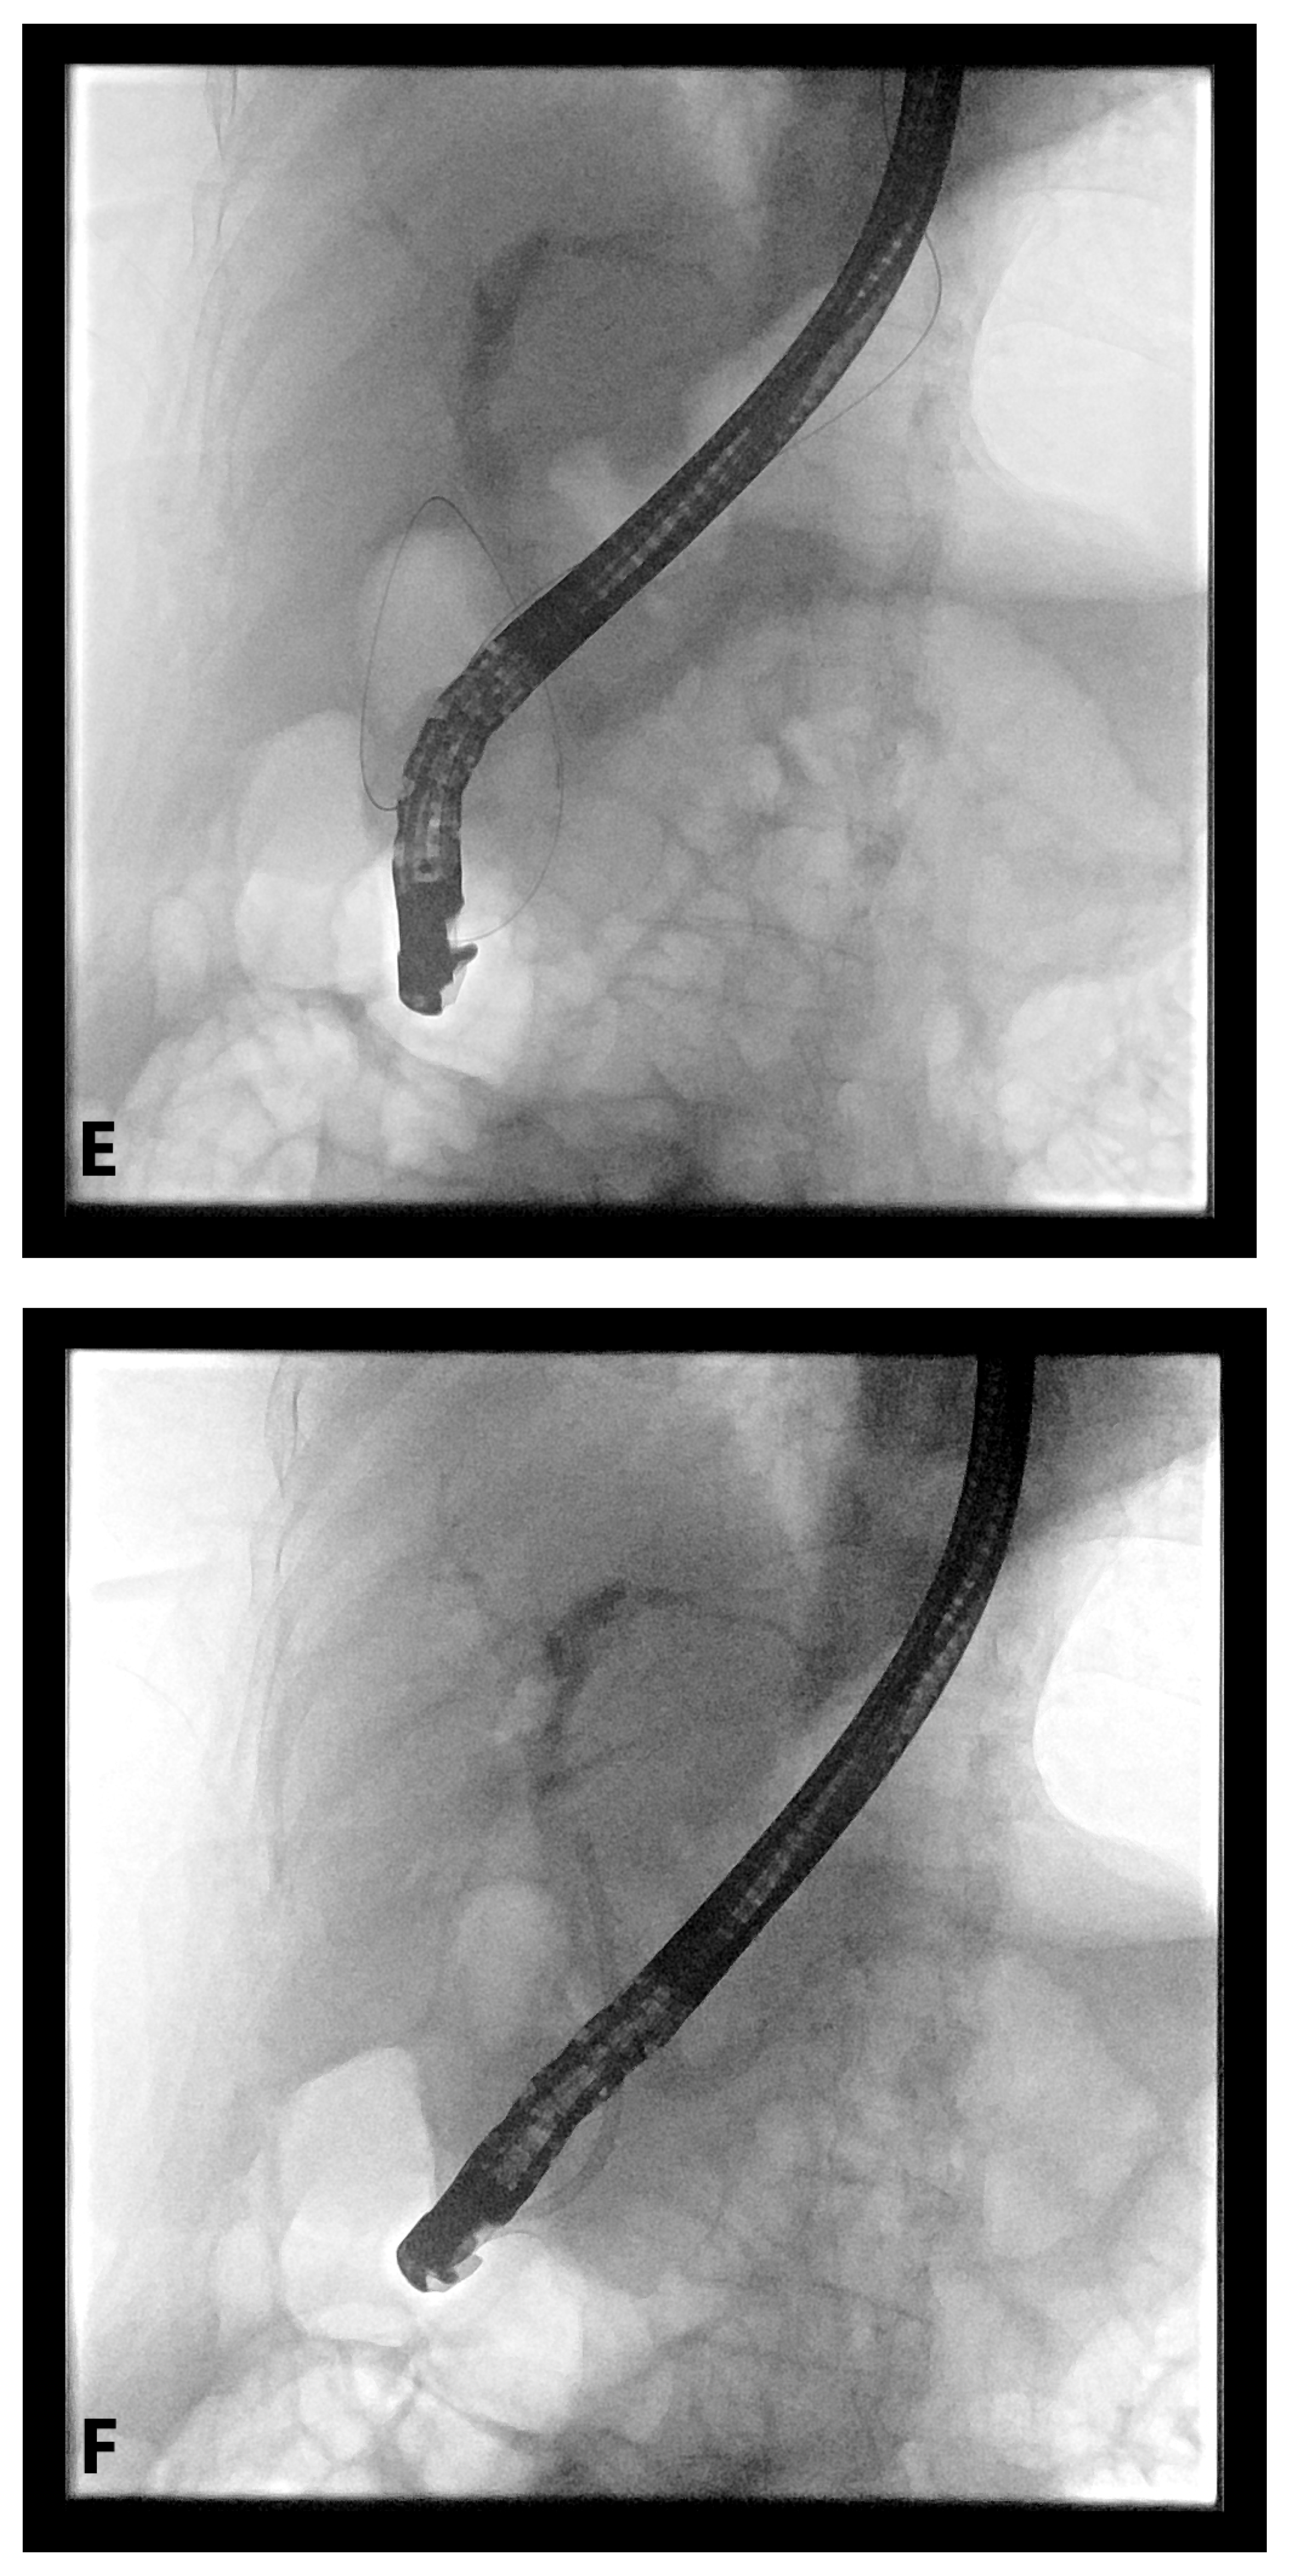

4. EUS-Guided Rendezvous (EUS-RV) Technique